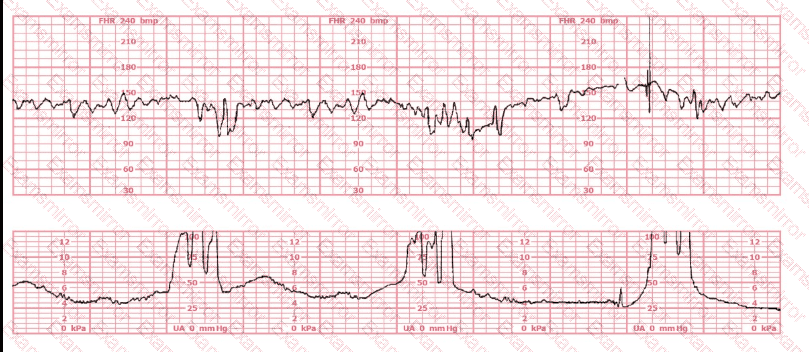

A woman (G1P0) arrives in triage with a pain score of 4/10 at 39-weeks gestation. The fetal heart rate tracing shown is obtained. The best intervention is to:

The baseline fetal heart rate in this tracing is:

What is the appropriate interpretation of this tracing?

(Full question)